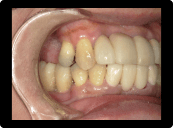

歯周病の治療例

奥歯の重度歯周病は保存困難のため抜歯してインプラント治療。残す歯は歯周病中等度であったため、歯周基本治療歯周外科治療を含めて行い、歯茎からの出血などはなくなった。

BEFORE

AFTER

症例概要

年代・性別

50代 女性

主訴

全体の歯茎から出血する、奥歯が揺れて噛めないことを主訴に来院されました。

治療内容

全顎歯周外科治療(保険治療)+奥歯インプラント治療4本

治療期間

6ヶ月

治療のリスク

歯肉退縮のリスクがあります

治療費用

約160万円